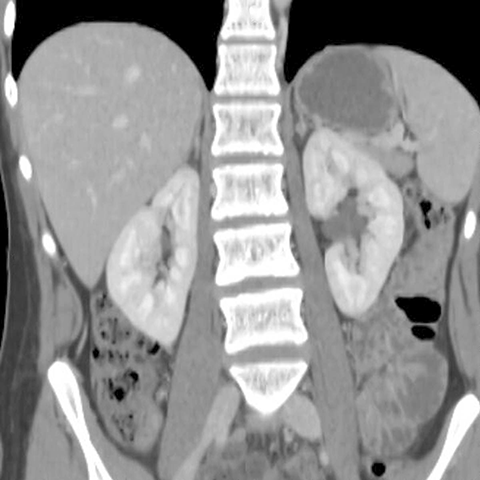

Coronal image of kidneys, CT